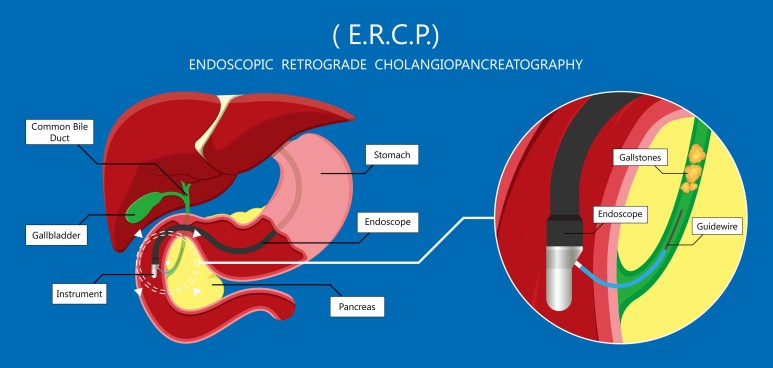

배쇄성 황달이 발생하는 원인은 다양한 총담관석, 담관협착, 담관 내 기생충,

Mirizzi 증후군, 원발성 경화 담관염, 췌장염, 혈액 담즙증 등을 들 수 있습니다.

또한 악성 질병에 해당하는 버터 팽대부 종양, 췌장암, 담관암, 십이지장암, 림프절과 간 전이로 담관을 압박하는 경우도 원인이 됩니다.

폐쇄성 황달이 나오는 원인은 담관이 막혀서 시작됩니다.

담관이 막혀 담관의 확장이 이루어지는데 처음에는 정상으로 보이는 경우가 있으나 시간이 지나면 문제가 발생합니다.

담관 담석과 양성 협착의 경우 보다 종양으로 인하여 담관이 막힐 경우 담관 확장이 더욱 심해집니다.

이렇게 담관이 확장된 경우에는 배액을 시행하면 담관의 크기가 이전과 같이 정상으로 돌아갑니다.